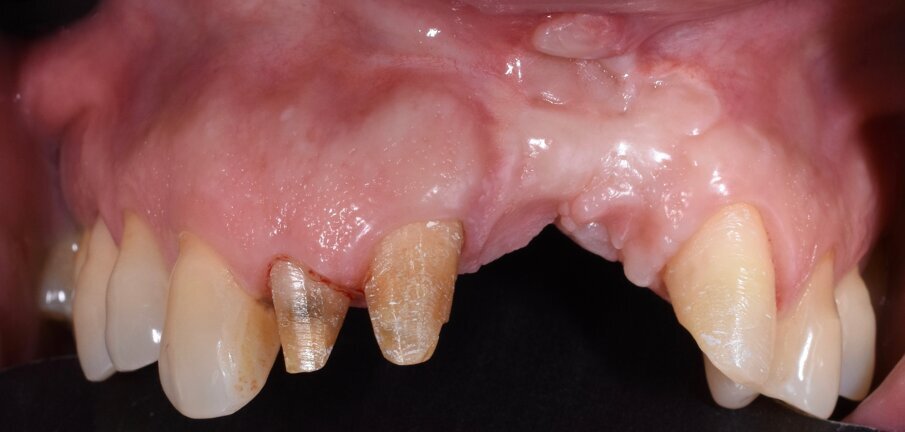

In questo articolo presentiamo un caso clinico che dimostra come il posizionamento improprio di un impianto può rendere impossibile la riabilitazione protesica, che richiede una nuova pianificazione chirurgica e riabilitativa per ottenere l’estetica desiderata. La paziente si presenta alla nostra osservazione con una riabilitazione protesica incongrua, con flangia in resina, a supporto dentale ed implantare, con la presenza di un impianto in posizione 2.1 vestibolarizzato e con l’emergenza nel fornice, in mucosa alveolare. Dalla valutazione della Tac si evince la posizione errata dell’impianto e la perdita consistente in senso trasversale della compagine ossea (Figg. 1, 2). Pertanto si opta per il seguente piano di trattamento che prevede: rimozione dell’impianto e preparazione protesica dell’elemento 2.3, confezionamento di un primo provvisorio a supporto dentale che servirà a guidare la guarigione dei tessuti (Figg. 3-7). A distanza di 4 mesi si procede a un innesto epitelio connettivale libero con prelievo dal palato per compensare il gap dei tessuti molli in senso trasversale, quindi viene ribasato il provvisorio in modo tale da favorire la guarigione dei tessuti (Figg. 8-11). A 9 mesi dalla maturazione dei tessuti si procede alla finalizzazione protesica fissa a supporto dentale (Figg. 12-14).

Fig. 1 - Situazione clinica iniziale.